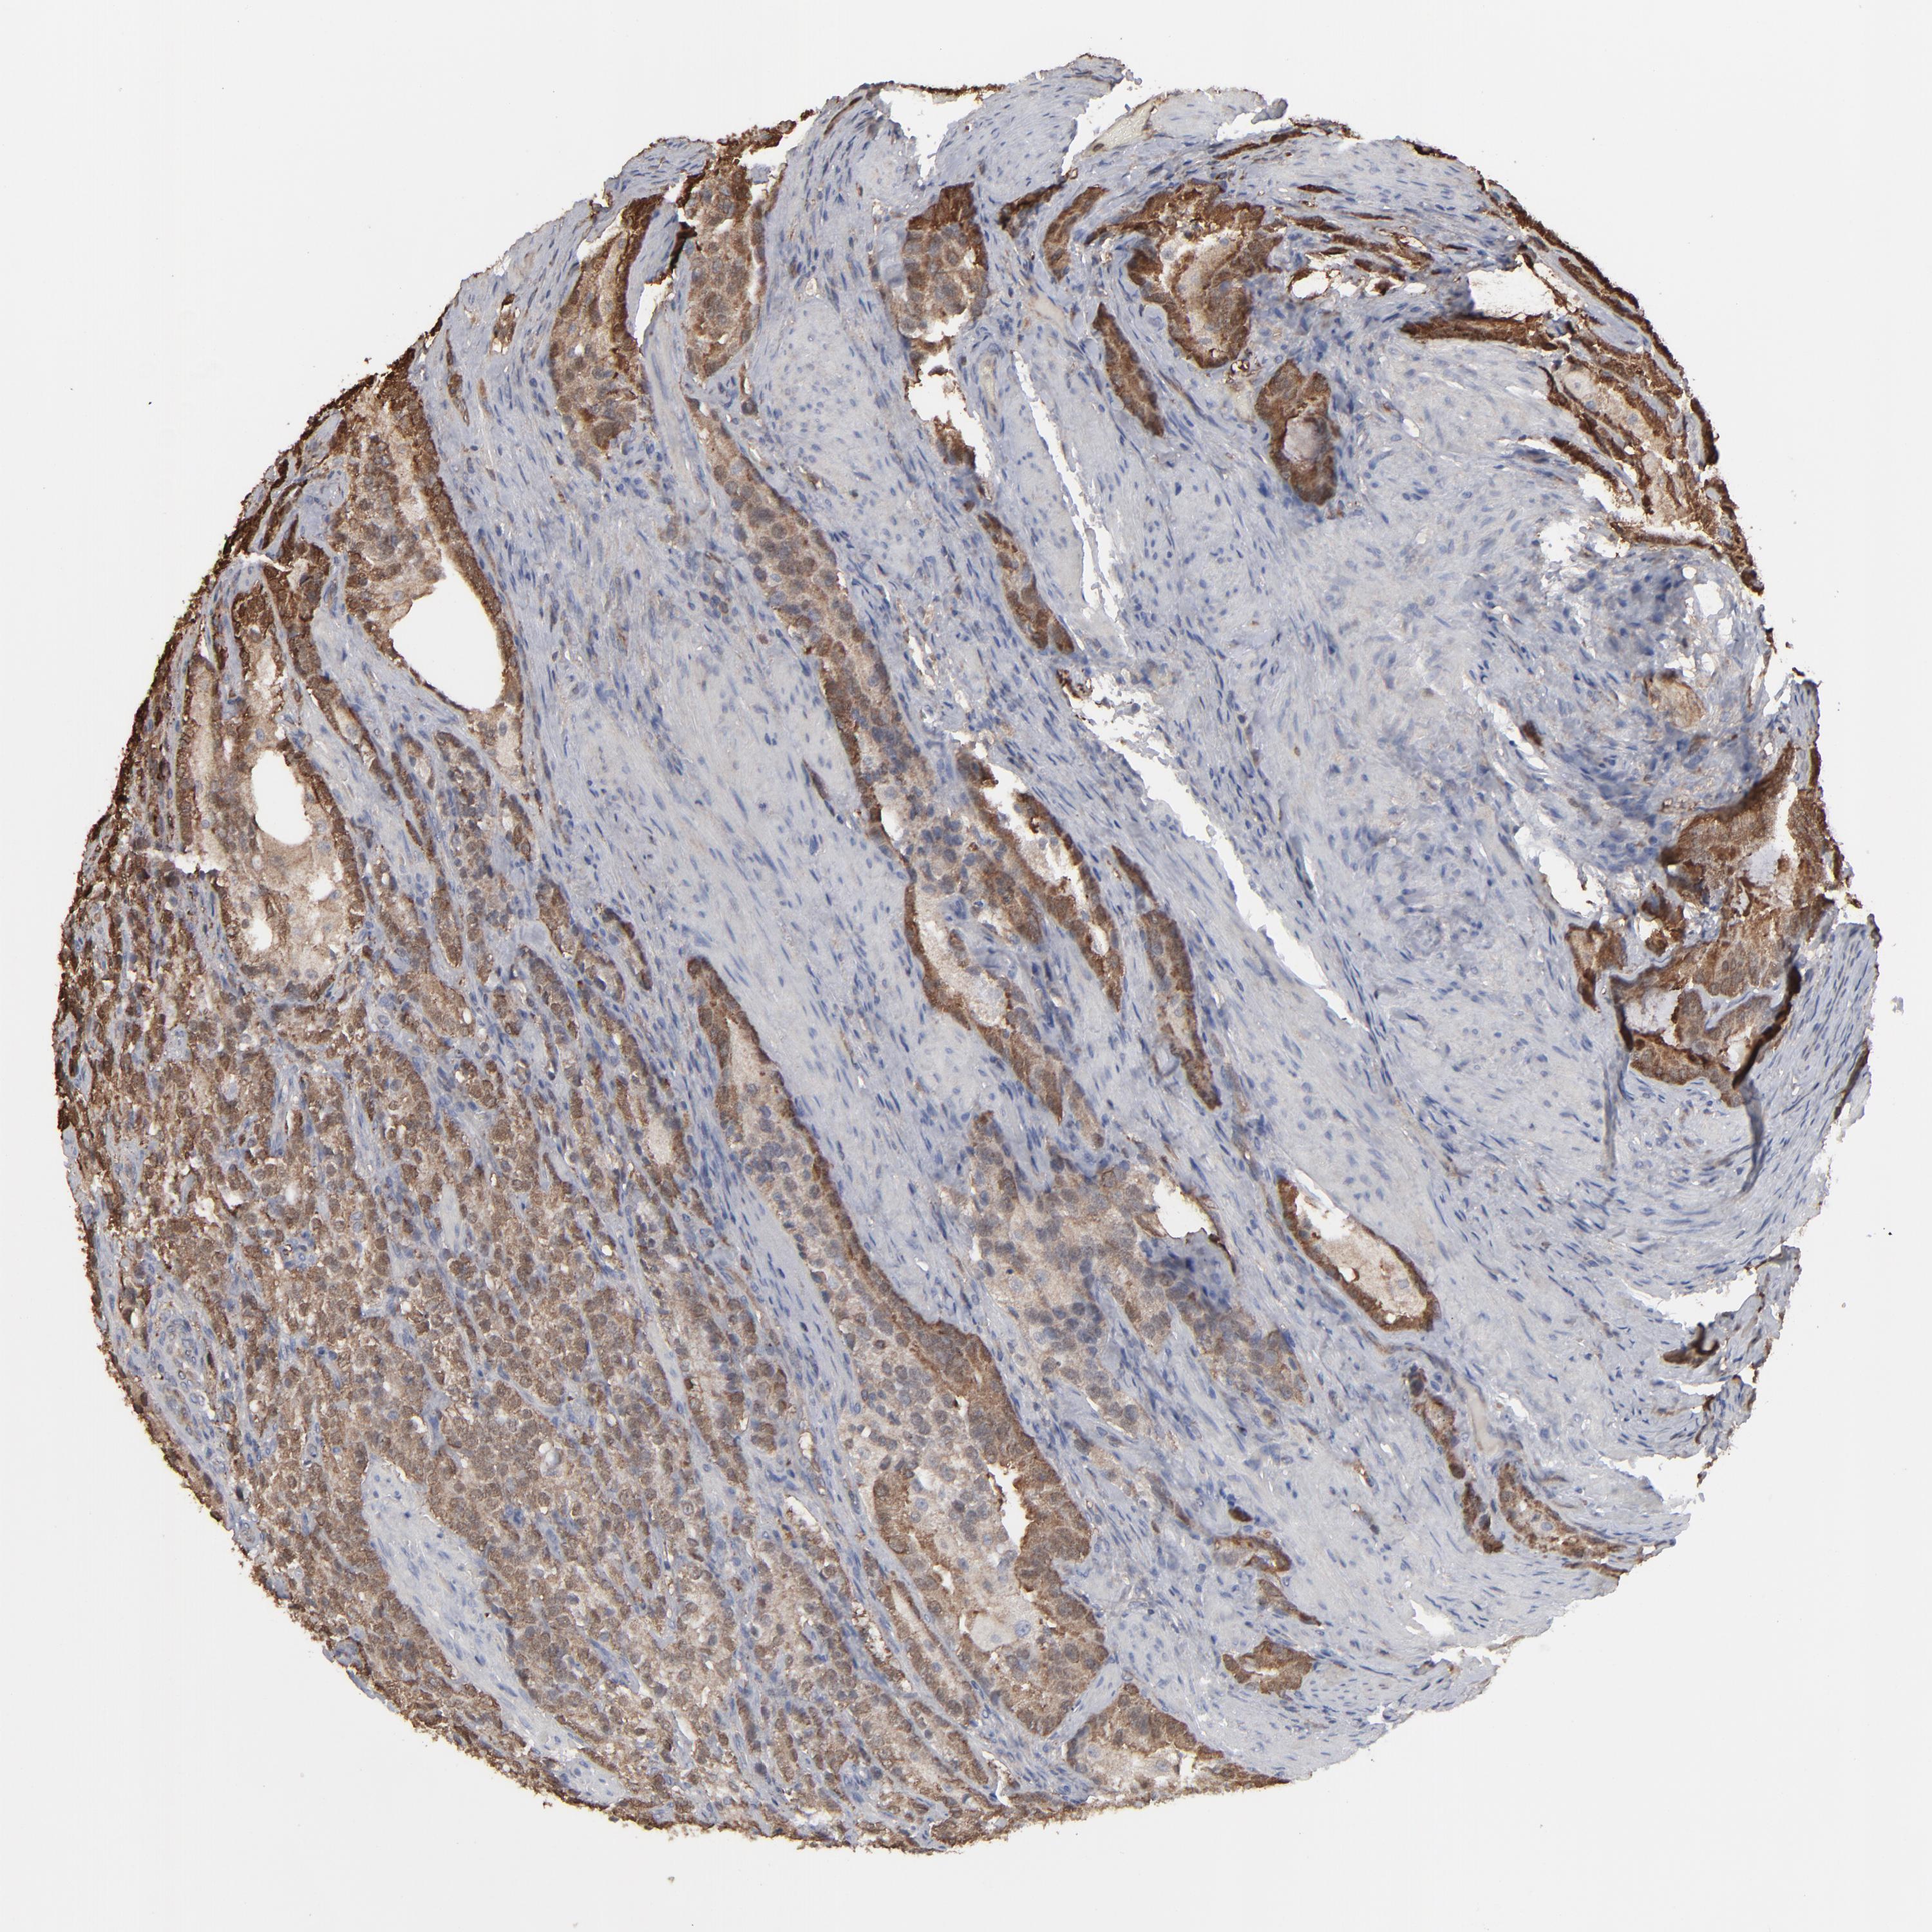

PROSTATE CANCER - Protein expressioni

A mouse-over function shows sample information and annotation data. Click on an image to view it in a full screen mode. Samples can be filtered based on level of antibody staining by selecting one or several of the following categories: high, medium, low and not detected. The assay and annotation is described here.

Antibody stainingi

Antibody staining in the annotated cell types in the current human tissue is reported as not detected, low, medium, or high, based on conventional immunohistochemistry profiling in selected tissues. This score is based on the combination of the staining intensity and fraction of stained cells.

Each image is clickable and will lead to virtual microscopy that enables deeper exploration of all samples and also displays staining intensity scores, fraction scores and subcellular localization as well as patient and tissue information for each sample.

Antibody HPA008467

Antibody HPA041113

Antibody CAB002169

Antibody CAB076057

Staining

High

Medium

Low

Not detected

Intensity

Strong

Moderate

Weak

Negative

Quantity

>75%

75%-25%

<25%

None

Location

Nuclear

Cytoplasmic/membranous

Cytoplasmic/membranous,nuclear

Adenocarcinoma, Low grade

Adenocarcinoma, High grade

Adenocarcinoma, NOS

Adenocarcinoma, Medium grade